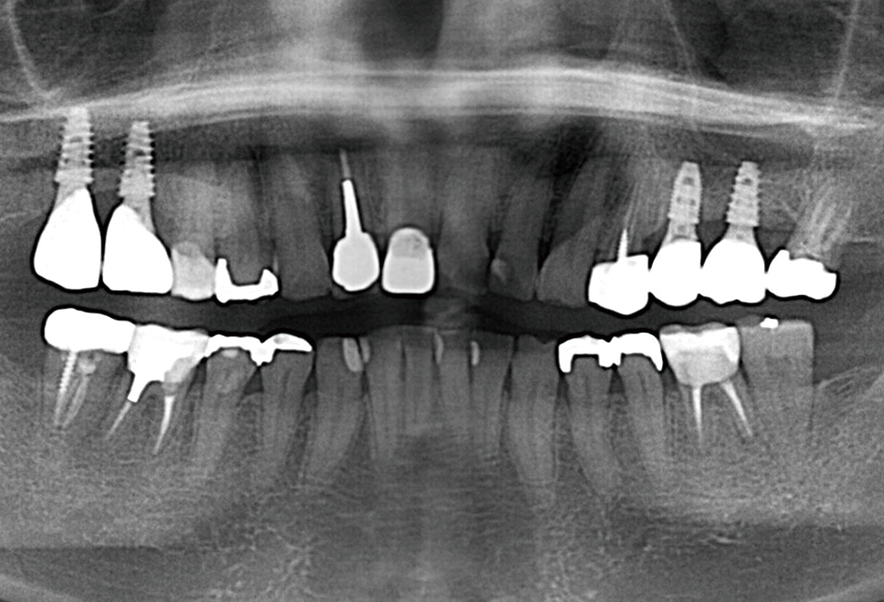

インプラント骨造成

Before

After